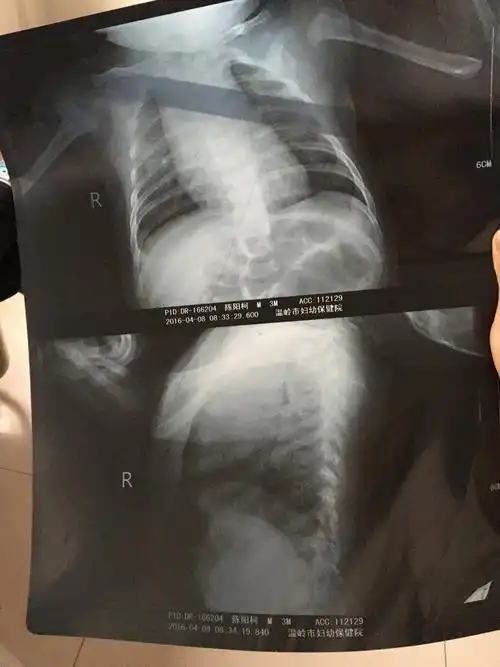

三个月宝宝肺炎住院三天了,刚开始是咳嗽拍片诊断肺炎的,住院第二天